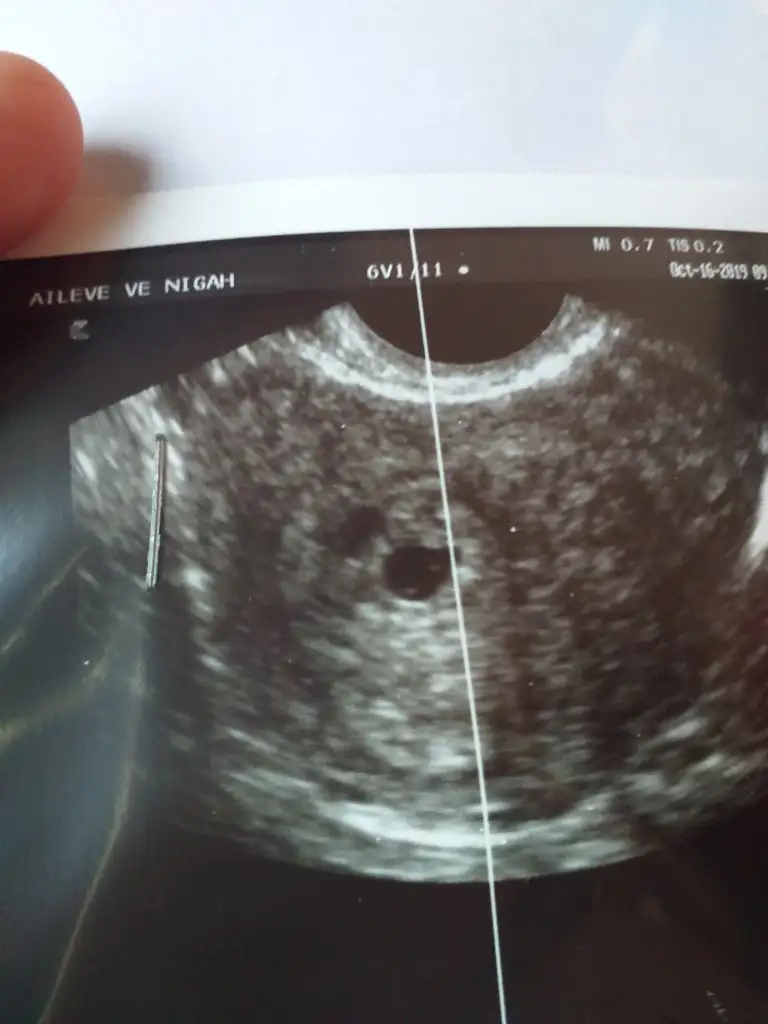

Nub için 11 yada 12 hafta kese için 6 yada 7 hafta usgnub icin erken ama kese pozisyon vs gore tahmini olan var mi? 9+4

Eki Görüntüle 2546197 Eki Görüntüle 2546198